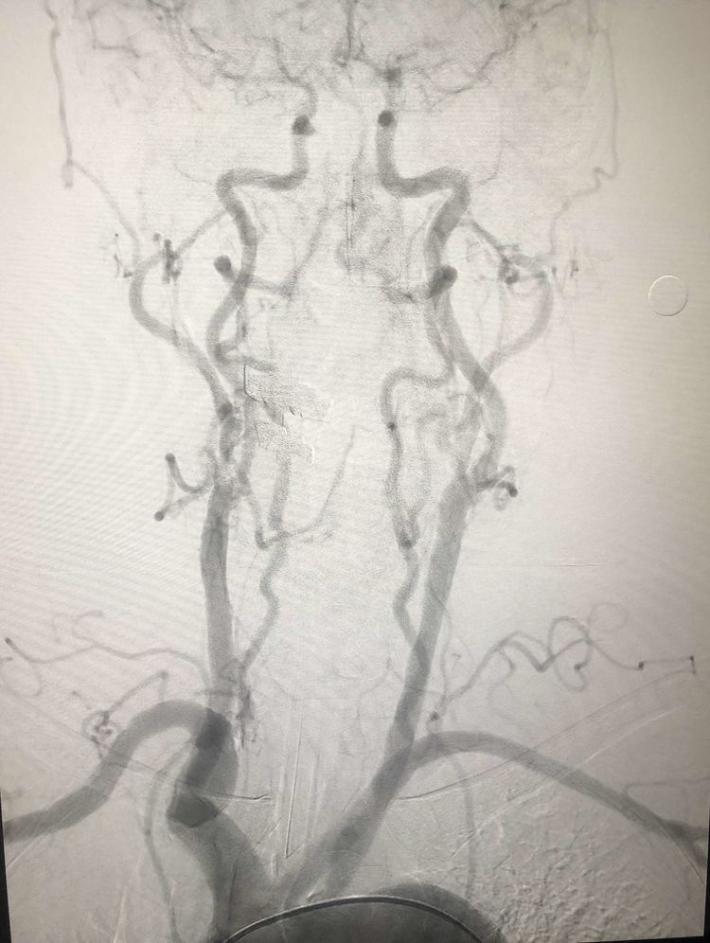

入院后75min,股动脉穿刺成功,后循环造影及右侧颈内动脉正侧位。

双侧颈内动脉

双侧椎动脉

右侧椎动脉造影:基底动脉中段充盈缺损,基底动脉尖丢失。提示基底动脉中段原位狭窄基础上血栓形成,血栓脱落栓塞基底尖。